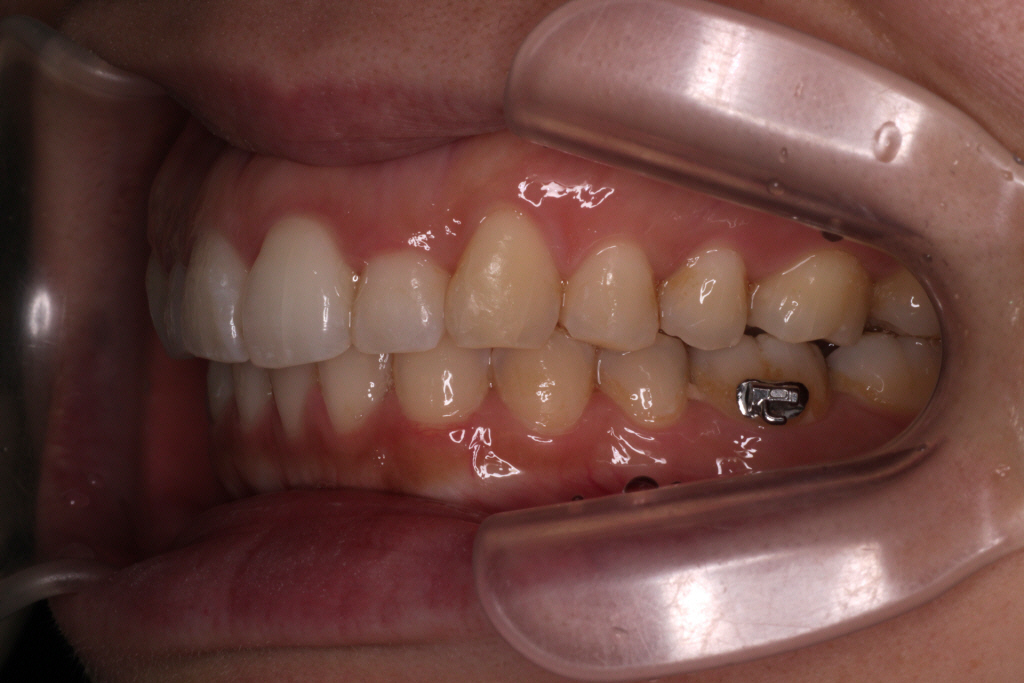

こちらが初診時の口腔内写真です。

上の歯と下の歯の中心がずれています。

また、通常「下の歯2歯に対し上の歯が1歯」というのが正常な歯並びですが

この患者様の場合、右側のみ下の歯が1歯に対し上の歯が1歯になっている事が分かります。

つまり右の咬み合わせは出っ歯の咬み合わせなので上の歯を後ろに下げる必要があります。

診断:上顎前突・上顎前歯部叢生・下顎左側切歯先天欠如